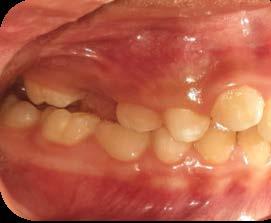

El canino divide su cara vestibular en 2 vertientes, una mesial que se continúa con los incisivos y otra distal que se alinea con los dientes posteriores, razón por la cual su ausencia genera alteraciones muy importantes en la oclusión y la estabilidad fisiológica del sistema estomatognático (Figura 3).

La incidencia de inclusión en los caninos superiores e inferiores tiene diferentes etiologías y similitudes. En ambos casos, el motivo principal se deriva de razones propias por su anatomía, tamaño en volumen coronal y largo de la raíz; sumado a esto, su ubicación lejana intraósea respecto al arco dental, desde la germinación y/o inicio de formación y desarrollo y, hasta alcanzar la erupción (Figura 4).

Respecto a los caninos inferiores permanentes, presentan con mayor frecuencia una posición con mayor tendencia a la inclusión, en el aspecto bucal del arco dental que los superiores, según se muestra en estadísticas con valores de 4% de prevalencia.45